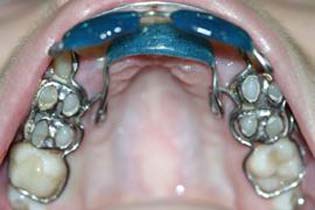

Аппараты содержат верхнечелюстную опору, на которой через ортодонтические пружины фиксируются опорноудерживающие каркасы боковых зубов и наклонная пластина (плоскость) с накусочной площадкой для резцов обеих челюстей (Фиг. 1, 3 Маилян 7.2). Последняя контактирует с твердым нёбом лишь только в пределах резцовой кости. Конструкция аппарата позволяет сочетать трансверсальный рост альвеолярного отростка верхней челюсти с эффективным воздействием сил жевательных мышц и пружин на наклонную пластину. Этим достигается зубоальвеолярная интрузия и протрузия резцов обеих челюстей, сочетающаяся с поднятием в переднем отделе твердого неба в области резцовой кости. Наклонная плоскость также способствует нормализации положения нижней челюсти и зубоальвеолярному удлинению в его боковых сегментах. На Фиг. 3 показаны силовые векторы воздействия аппаратов в области резцов. Вариантом исполнения аппарата может быть конструкция, где пластмасса наклонной пластины не контактирует с твердым нёбом, а опорноудерживающие каркасы боковых зубов соединены между собой вестибулярной дугой.

При медио-латеральном смещении верхних резцов лечение проводится аппаратом, обеспечивающим независимое друг от друга перемещение верхних и нижних резцов. Конструкция отличается от вышеописанного аппарата тем, что наклонная пластина с накусочной площадкой в области верхних резцов контактирует только с их режущими краями, а на нёбной опоре через пружины закреплена рассредоточенная по высоте верхних резцов замкнутая вестибулолингвальная дуга или каркас (Фиг. 2, 4.). Данная конструкция позволяет достичь перемещения фронтальных зубов в трех направлениях, а интенсификации данного процесса способствует трансверсальный рост альвеолярного отростка. На Фиг. 4 показаны силовые векторы воздействия аппарата в области резцов. При малой высоте коронок боковых зубов контакт резцов с накусочной площадкой наклонной пластины может привести к сбросу аппарата, что можно предотвратить выполнением элементов крепления со съемными и несъемными деталями (Фиг. 2).

Применяются для лечения дистально глубокого прикуса. Базисы аппаратов представляют собой небную опору в виде дугового проволочного бюгеля или каркаса на которой непосредственно закреплена наклонная пластина (плоскость), а через ортодонтические пружины опорноудерживающие каркасы зубов. Последние соединены между собой вестибулярной дугой. При малой высоте коронок боковых зубов контакт резцов с накусочной площадкой наклонной пластины может привести к сбросу аппарата, что можно предотвратить выполнением элементов крепления со съемными и несъемными деталями (см. Фиг.2). Опорноудерживающие каркасы аппаратов могут снабжаться дугами для фиксации скоб щечных пластин (см Фиг. 5).